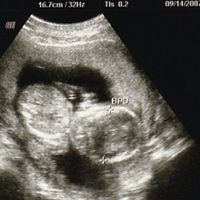

妊娠11週~14週 エコー超音波検査について 初妊娠10週目です。 昨日検診に行って次回は一ヵ月後でいいと言われました。 帰宅後パソコンなどで11週~14週はエコーで胎児の後頚浮腫などが発見しやすく染色体異常や心臓病などの可能性もわかるとありました。 頭大横径は261mm前後 妊娠14週に入ったばかりの赤ちゃんの頭大横径(BPD※)は、個人差はありますが、261mm前後*1となります。 ※妊娠中期以降になると、赤ちゃんは子宮内で手足を曲げているため、身長の推定は困難となります。 そこで、赤ちゃんの発育を確認する指標のひとつとして頭大横径(BPD:頭の最も大きい横幅)が用いられるようになります。 安定期といわれる妊娠5ヶ月に突入した16週目には胎児は約100gくらいになり、骨もしっかりして関節も完成し、背骨やあばら骨もエコーでみることができます。 耳もしっかり聞こえるようになるのでお母さんの声に反応することも。 また、脳の神経系が発達してくる時期で、自分の医師で手足を動かしたり、物事を記憶することもできるようになります。 出典

妊娠13週で異常が妊娠継続を決断し、悲しい別れをした夫婦の11年後 出生前診断と母たち(17)年月 河合 蘭 頭大横径は261mm前後 妊娠14週に入ったばかりの赤ちゃんの頭大横径(BPD※)は、個人差はありますが、261mm前後*1となります。 ※妊娠中期以降になると、赤ちゃんは子宮内で手足を曲げているため、身長の推定は困難となります。 そこで、赤ちゃんの発育を確認する指標のひとつとして頭大横径(BPD:頭の最も大きい横幅)が用いられるようになります。14週の時に胎児専門のドクターにエコーをして頂き、今の所、週数通りで問題はなさそうとの事でした。 染色体異常を調べる検査をするべきか相談したところ、しなくても大丈夫でしょ。 と言われ安心していました。 しかし、色々調べていると18

妊娠16週5日(16w5d)で性別がわかった! 妊娠16週5日(16w5d)のエコー画像 妊娠16週で性別が男の子と確定したエコー画像 PR出産準備が10%オフ!Amazonベビーレジストリに登録しよう! 流産リスクなしの出生前検診って知ってる?胎児頭頸部の周囲に多胞性の嚢胞状エコー. 45XOの例. 染色体異常と関連する妊娠初期の超音波所見 胎児染色体異常と関連する超音波所見は2つに分けられる.ひとつは正常では見られ 領域が増大する3).妊娠11~14 週に最大幅を測定し,3mm以上